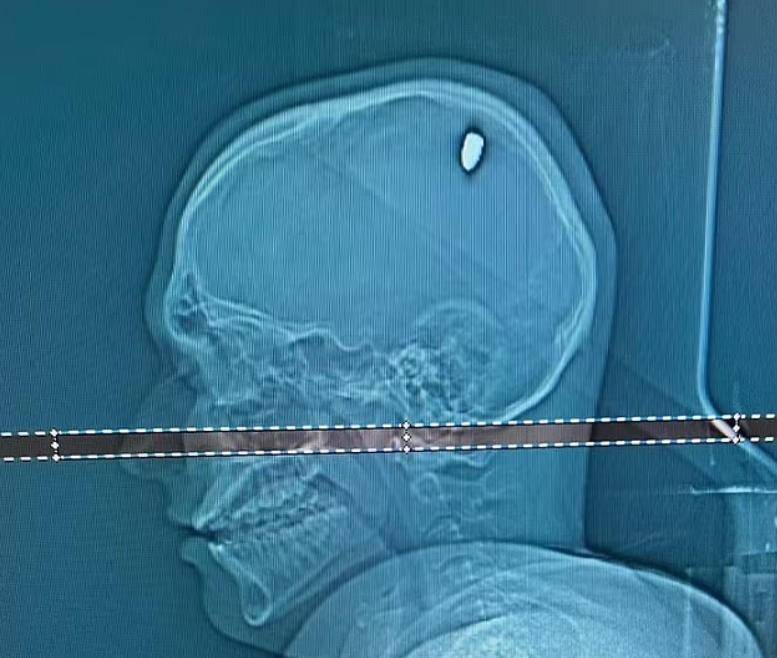

她丈夫后来带她去检查,医生用X光一照,确认那是半自动步枪的弹头,虽然锈蚀严重,但结构还能辨认。

CT一扫,医生差点从椅子上跳起来——一颗子弹正卡在他大脑左侧运动皮层附近,压迫控制右臂的神经通路。

注意,这时候距离中弹已经过去整整五天。

五天里,他喝酒、跳舞、游泳、开车,一切如常,除了头痛和手臂不适,完全没意识到自己脑袋里嵌着致命金属。

神经外科团队立刻安排手术,两小时后,子弹被完整取出。

主刀医生说,子弹穿透了颅骨,但没造成大范围脑组织破坏,属于“低速钝性穿透伤”。